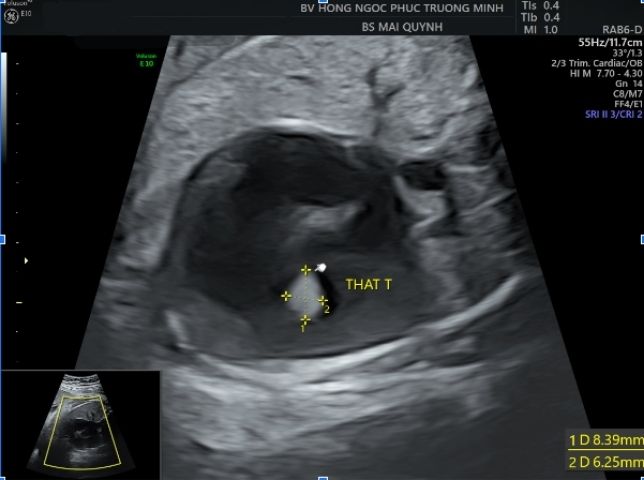

Hình ảnh thông liên thất ở thai 30 tuần với kĩ thuật 4D STIC tim thai.Siêu âm tim thai là một kỹ thuật chuyên sâu, ngoài kiến thức, kinh nghiệm và trình độ chuyên môn của các bác sĩ, trang thiết bị cũng là một phần rất quan trọng. Hiện nay, khoa Sản Phụ khoa - Bệnh viện Đa khoa Hồng Ngọc Phúc Trường Minh là cơ sở đầu tiên và duy nhất trên cả nước sở hữu máy siêu âm hiện đại nhất thế giới - Voluson Expert 22 của hãng GE Healthcare. Với công nghệ UltraHD, Augment, Shadow Reduction.... cùng các kĩ thuật tái tạo tim 3D, 4D STIC cho phép tăng độ chính xác trong chẩn đoán bất thường tim thai cũng như minh họa cho cha mẹ hình ảnh thai nhi một cách sinh động và trực quan nhất có thể.